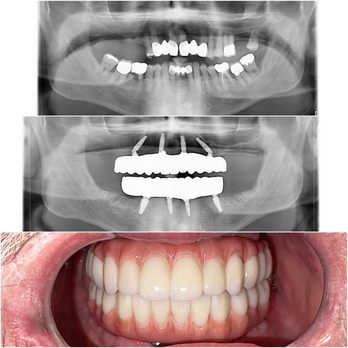

If you are searching for exceptional cosmetic dentists in a state-of-the-art dental practice in Roseville, California. You have found the right place. We also service the greater Sacramento area. As cosmetic dentists, Dr. Kwan and Dr. Hsu will provide you with a beautiful and functional smile that you’ve always dreamed of. At Nu Smile Roseville Dental, we pride ourselves on providing all guests with the most advanced cosmetic dentistry techniques and procedures, performed with the most cutting-edge technology, in a comfortable, relaxed setting.